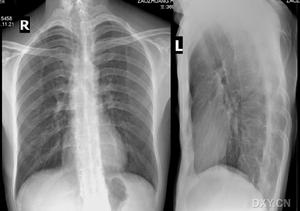

影像學檢查X線頸椎片和胸片可以排除頸肋、第7頸椎橫突過長、鎖骨、第一肋骨畸形或其它骨性病。都卜勒超聲可以發現血管受壓狹窄。血管造影可以確定狹窄和受壓的部位。CT和MRI是一種敏感且無侵害性的方法,對TOS的確診有一定幫助。Bilbey等報導了60%TOS患者CT檢查有異常發現。Akal等報導了3D-CT可以發現胸廓出口處的狹窄,有效顯示胸廓出口處各結構的關係。Xavier等在他們的研究中發現MRI對確定神經血管卡壓部位和引起卡壓的原因有幫助。